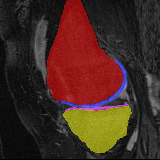

Moving

Target

Mono-0

Mono-5

DA-1

DA-5

Mono-200

Results: All trained networks are evaluated using Dice overlap scores between predictions and the manual segmentations for the segmentation network, or between the warped moving segmentations and the target segmentations for the registration network. Tabs. 1 and 2 show results for the knee and brain MRI experiments respectively in Dice scores (%). Fig. 2 shows examples of knee MRI registrations and brain MRI segmentations.

Knee results: On knee MRIs, our method improves segmentation scores over separately learned networks by about 1.2 and 0.5, and registration scores increase by about 3.1 and 3.0, when training with 5 and 10 manual segmentation respectively. Especially for the challenging cartilage structures, our joint learning boosts segmentation by 1.4 and 0.7, and registration by 5.5 and 5.2 for N=5 and N=10 respectively.

Qualitative results: DA achieves more anatomically consistent registrations than the mono-networks on the knee (Fig. 2) and Brain MRI samples (see supplementary material).